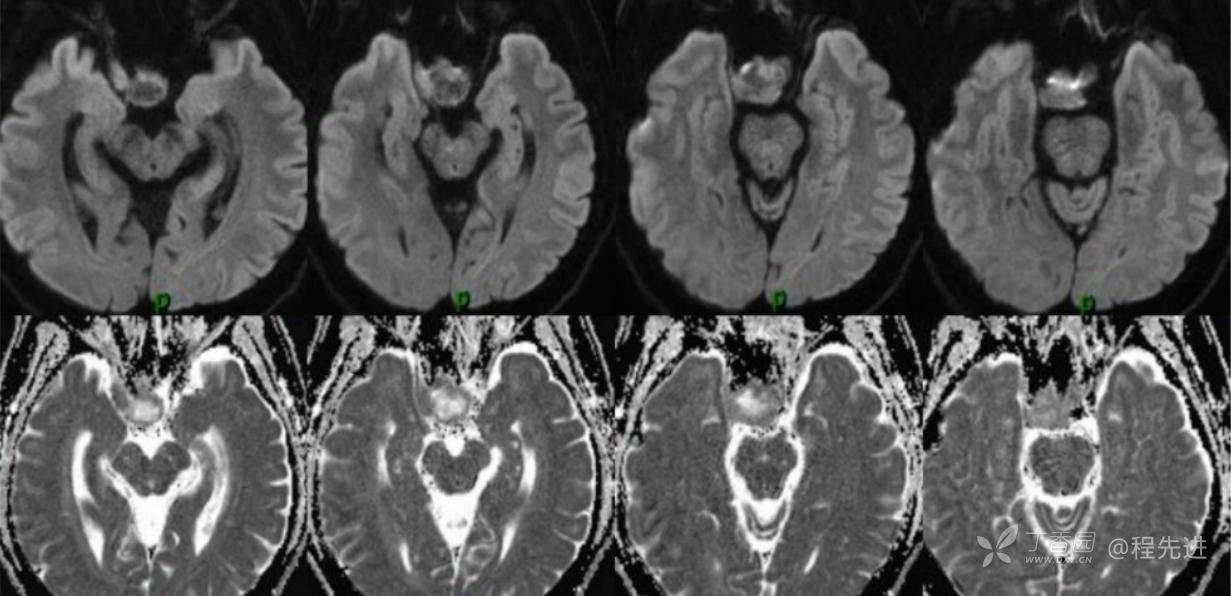

MR:

DWI及ADC图

T1+C